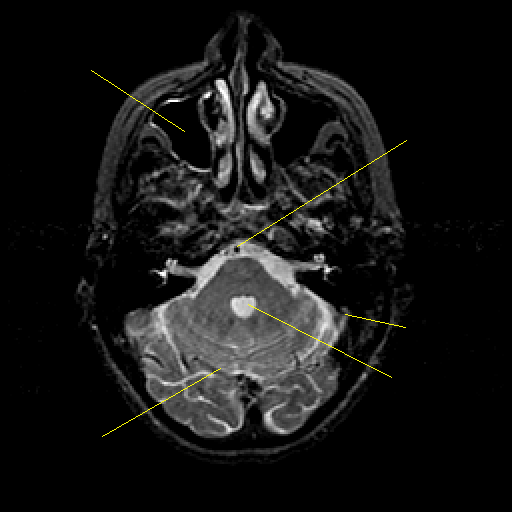

T2-weighted structural MR: Slice 14

Slice 14

Pointers

Labeled